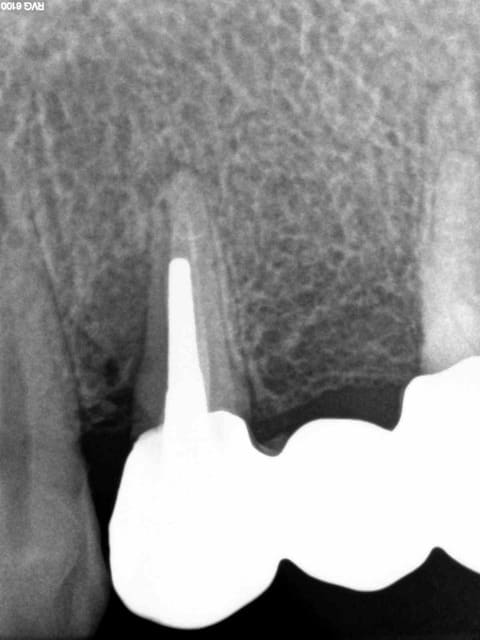

Patiente vue en 2011 et partie dans la nature........

.........Et revenue aujourd'hui en urgence avec un magnifique bridge CCAM-CMU + pulpite sur 26 en option. (bridge 1 mois). Option pèche sur 14 à venir sous l'ic également.

J'y ai collé un amalgame au pouce histoire de faire plus vrai.-)))))

Costaud le full zircone